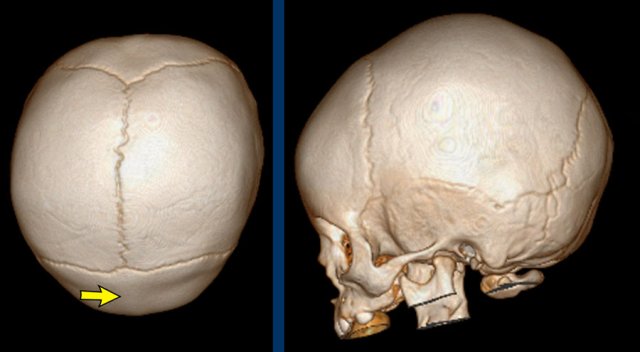

3D CT

The images show open sutures in a child with a physiologically closed metopic suture (arrow).

Images courtesy of Dr K.A. Eley and Dr C. Delso Images courtesy of Dr K.A. Eley and Dr C. Delso